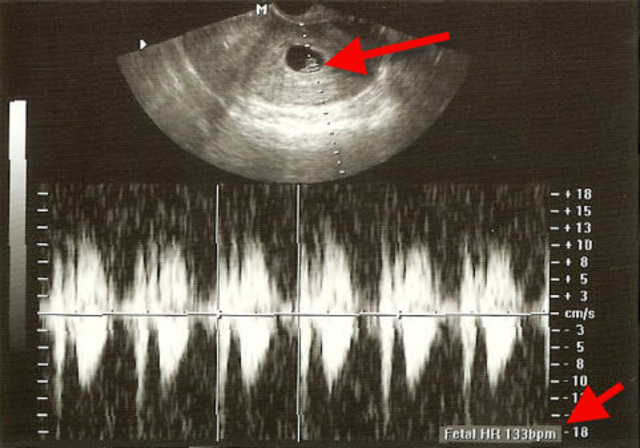

• Prenatal - Heartbeat

Prenatal - Heartbeat

'http://http://missedconceptions.wordpress.com/2007/11/' 5 weeks (3 weeks past conception) The heart begins beating at this time and within a week the heartbeat can be heard via ultrasound. The body of the embryo measures at about 1/4 inch. This is about the size of a sesame seed. The digestive system, spinal cord and the backbone are beginning to form. </a>